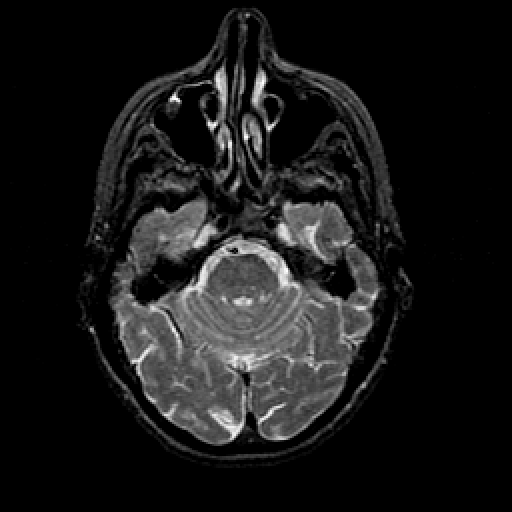

T2-weighted structural MR: Slice 16

Slice 16